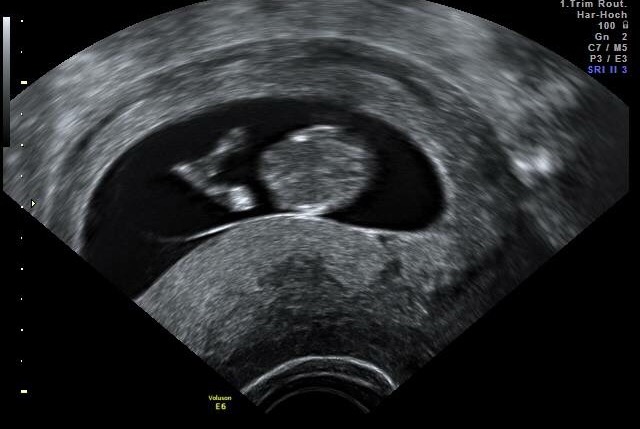

10w5d naša malá krevetka ♥